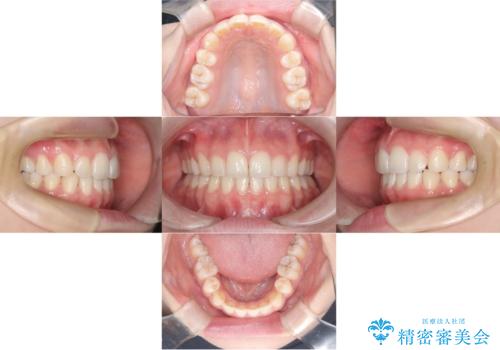

- 「歯のでこぼこと捻じれを治したい」を主訴に来院された患者様です。矯正検査の結果、上顎前歯がかなり唇側傾斜という結果になったので上下左右4番を抜歯をしワイヤー矯正で治療を行いました。

抜歯矯正でしたが順調に治療が進み2年で矯正治療を終えることが出来ました。歯のでこぼこや捻じれが治り、口元も下がって患者さんも大変満足されていました。